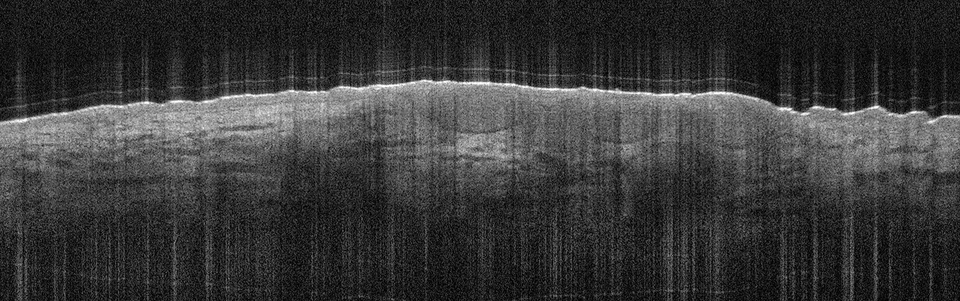

Die Tumorzellverbände des BCC erkennt man in der Aufnahme als signalarme, ovoide Nester mit dunk­lem Randsaum, die von hellem Stroma umgeben sind. Die Epidermis ist abgeflacht, Teleangiektasien kann man als kleine dunkle Löcher sehen. Eine aktinische Keratose sieht anders aus: In diesem Fall sind Hornschicht und Epidermis verdickt, oft sieht man auch weiße Streifen in der Hornschicht, so die Referentin. In Abgrenzung zum Plattenepithelkarzinom erscheint die dermoepidermale Junktion bei der aktinitischen Keratose intakt. Beim Plattenepithelkarzinom werden zudem helle Bereiche deutlich, bei denen es sich um Hornzysten handelt.

Das superfizielle BCC ist charakterisiert durch die oberflächlichen Tumornester, die wie Perlen an einer Kette aufgereiht von der Epidermis in die darunterliegende Dermis ragen. Das superfizielle BCC ist charakterisiert durch die oberflächlichen Tumornester, die wie Perlen an einer Kette aufgereiht von der Epidermis in die darunterliegende Dermis ragen. © Prof. Dr. Julia Welzel